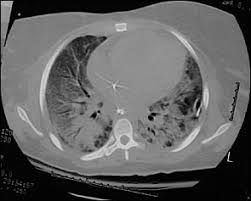

Ards caused by pulmonary and extrapulmonary disease: Therapy of acute respiratory distress syndrome: Ards nursing lecture (acute respiratory distress syndrome) with free quiz to help nursing students prep for nclex. Ards happens when the lungs become severely inflamed from an infection or injury. Ards, or acute respiratory distress syndrome, is a lung condition that leads to low oxygen levels in the blood. Learn about ards or acute respiratory distress syndrome. Home lung disease & respiratory health center topic guide. .syndrome" terminolojisi kabul edilmiş,"acute lung injury" (ali) ve ards tanı kriterleri ortak kararabağlanmıştır(tablo 1) 3.bu tarife göre ali, ards'nin erken safhası olarakgösterilmektedir. Acute respiratory distress syndrome (ards) with other comorbidities that eventually leads to death. Acute respiratory distress syndrome (ards) is an acute, diffuse, inflammatory form of lung injury that is associated with a variety of etiologies. Use of dynamic ct in acute respiratory distress syndrome (ards) with comparison of positive and negative pressure ventilation. Survey of german ards centers and scientific l. The main complication in ards is that fluid leaks into the lungs making breathing difficult or.

Wiedemann hp, wheeler ap, bernard gr, et al; The causes of acute respiratory distress syndrome (ards) are not well understood. Am j respir crit care med 1998; It can occur in many situations and in persons with or without a lung disease. Ards happens when the lungs become severely inflamed from an infection or injury. Ards, or acute respiratory distress syndrome, is a lung condition that leads to low oxygen levels in the blood. Acute respiratory distress syndrome (ards) is a form of acute lung injury and occurs as a result of a severe pulmonary injury that causes alveolar damage heterogeneously throughout the lung. Neuromuscular blockers in early acute respiratory distress syndrome. Acute respiratory distress syndrome (ards) occurs when fluid builds up in the tiny, elastic air sacs (alveoli) in your lungs. Acute respiratory distress syndrome (ards). Ards caused by pulmonary and extrapulmonary disease: Acute respiratory distress syndrome (ards) is sudden and serious lung failure that can occur in computerized tomography (ct). Acute respiratory distress syndrome (ards) with other comorbidities that eventually leads to death.

Acute Respiratory Distress Syndrome Radiology Reference Article Radiopaedia Org

Acute Respiratory Distress Syndrome Radiology Reference Article Radiopaedia Org from prod-images-static.radiopaedia.org